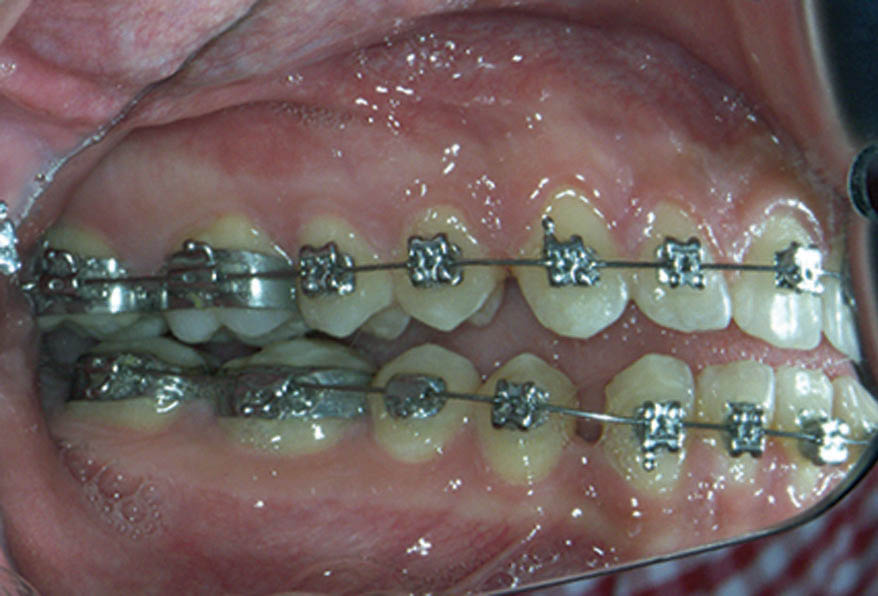

البته در حین درمان بهخاطر تماسهای اکلوزالی احتمال کنده شدن براکتها وجود دارد، مخصوصاً پرمولرهای دوم پائین بیمار. به همین جهت برای این دندان باکال تیوب درست کردهاند که بالچه اکلوزالی نداشته باشد، لذا ضربه دندانهای بالا روی آن کمتر میشود. از طرفی در زمان بسته شدن فضا اصطکاک در باکال تیوب به مراتب کمتر از براکتی است که اورینگ دارد، لذا سرعت بسته شدن فضا نیز بیشتر میشود (شکل 80-1).

شکل 80-1: تیوب پرمولر دوم